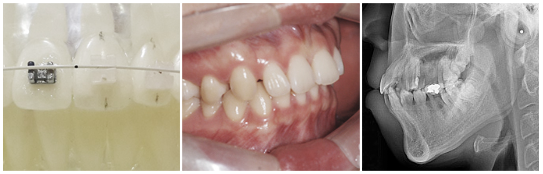

치아교정 내게 맞는 치아교정

얼굴 모습의 조화와 아름다운 미소까지 선사하는 서울라이프치과

DIO navi 3D 치아교정

3D 디지털 치아교정